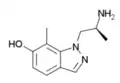

A number of related compounds are known, with a similar structure but having the indole core flipped and/or replaced with related cores such as indoline, indazole, benzothiophene, or benzofuran. These similarly are primarily active as agonists at the 5-HT2 family of serotonin receptors, with applications in the treatment of glaucoma, cluster headaches or as anorectics.

Ro60-0175 | (S)-(6-chloro-5-fluoro-1H-indol-1-yl)propan-2-amine | 169675-09-6 |

|